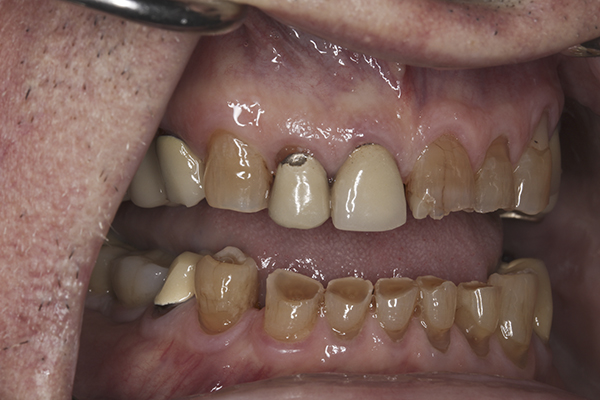

(10.) Preoperative anterior, closed view. Note the end-to-end occlusion of the anterior teeth and the wear on the incisors and centrals resulting in no anterior or canine guidance.

Figure 10

A complete examination was performed. The patient showed no signs of joint dysfunction and there was no tenderness to palpation of any of his muscles of mastication. His mandibular range of motion was within normal limits and his function was completely comfortable. Loading of the joints in centric relation was possible with no signs of tension or tenderness. The first point of tooth contact in centric relation was noted on tooth No. 3 with a 1 mm slide forward from centric relation into maximum intercuspation. Doppler auscultation of the joints showed no signs of clicking/popping or crepitus. Examination of the teeth showed significant wear, abfractions, and erosion into the dentin of the anterior teeth. The patient also had a history of fractured porcelain on his posterior restorations and crowns coming loose. An evaluation of his occlusion revealed that the patient lacked stable centric stops on all teeth. Anterior and canine guidance was non-existent, which led to no separation of the posterior teeth during protrusive and lateral movements. His maxillary and mandibular occlusal planes were also not ideal. The patient reported no airway issues while sleeping and he had a Class 1 Mallampati score. The patient was advised to consult with his physician to evaluate for an acid reflux issue.

A complete set of records was taken, including diagnostic photographs (Figure 3 through Figure 16), diagnostic impressions, a centric relation bite record, and a facebow transfer. The models were mounted onto an articulator and, along with the photographs, a preliminary workup of the case was completed. An ideal treatment plan consisting of a fullmouth rehabilitation with full-coverage restorations to idealize the planes of occlusion and to properly restore the anterior teeth was presented to the patient. The patient was not interested in extensive work on his posterior teeth because of his age and the fact that he was only interested in “something that will last another 10 years because that’s about how long I’ll be around.” He was only concerned with addressing the anterior teeth and would not accept a treatment plan replacing the restorations on his posterior teeth. Because the author wanted to help the patient with his esthetic concern while still addressing the functional issues, an alternative compromise treatment plan was agreed upon, which involved definitive full coverage restorations in the anterior and composite bonding in the posterior. The patient was fully aware that this treatment plan was a compromise and that the posterior composites will most likely require repair over time. By stabilizing the anterior contacts, anterior guidance, and canine guidance, the author felt comfortable placing bonded composite restorations on the posterior teeth to improve the plane of occlusion. The author also suggested the use of a nighttime occlusal appliance, but the patient refused this option. A guard worn at night would have increased the longevity of the posterior composites, as well as further protected the anterior restorations.